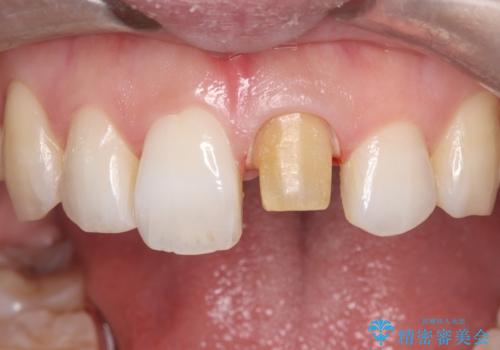

- 「以前、他院で神経を取った前歯がだんだん黒ずんできた」という見た目の改善を主訴にご来院されました。 診査の結果、神経を取り除いた後の歯(失活歯)特有の変色が起きており、さらに根の先端にわずかな影が見られたため、内部で感染が起きている可能性がありました。

そこで、まずは土台を外して根の内部をきれいにする再根管治療を行い、基礎をやり直した上で、透明感の高いオールセラミッククラウンで被せ直す治療計画を立案。単に白くするだけでなく、再発を防ぎ、長期的に美しい状態を保つことを目指しました。